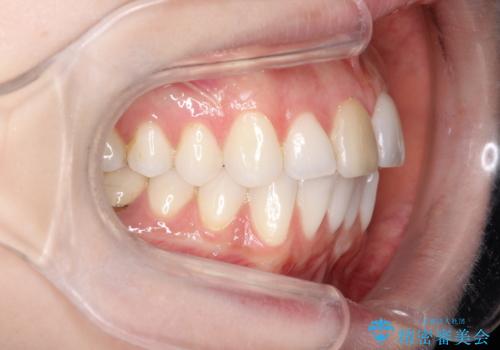

インビザラインによる非抜歯での八重歯の矯正

- 左上の八重歯と、上の歯のがたつきを主訴に来院されました。

上の奥歯を後方に移動させてスペースを作るのと、歯と歯の間をわずかに削り歯を並べる計画としました。

非常に強力的な患者様であったので、上下の正中も合わせ、ガタガタも改善することができました。